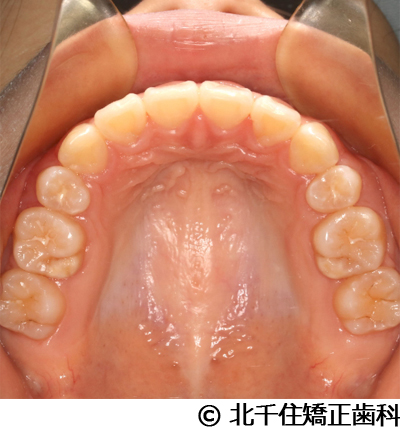

【症例5】上顎前突

- 治療前

- 治療後

- 治療名

- 上顎前突

- 費用

- 1,263,600円(税込)

- 期間

- 2年8ヵ月

- 治療回数

- 32回

- 通院頻度

- 1ヵ月ごと

- 年齢

- 13歳3ヵ月(初診時)

治療内容

-

患者様の症状

主訴:出っ歯

治療方法

骨格性の上顎前突、ヘッドギアを併用して上下顎第一小臼歯4本抜歯してワイヤー矯正。

治療結果

骨格性上顎前突に対し、ヘッドギアおよび抜歯を併用した矯正治療により歯列および咬合関係の調整を行った症例である。

治療後は保定装置を使用し、歯列および咬合の安定維持を目的として定期的な経過観察を行っている。

※治療結果は個人差があります。

治療を行う上での注意点(リスク・副作用)

歯磨き不良に伴うカリエスや歯周病、歯根吸収など。